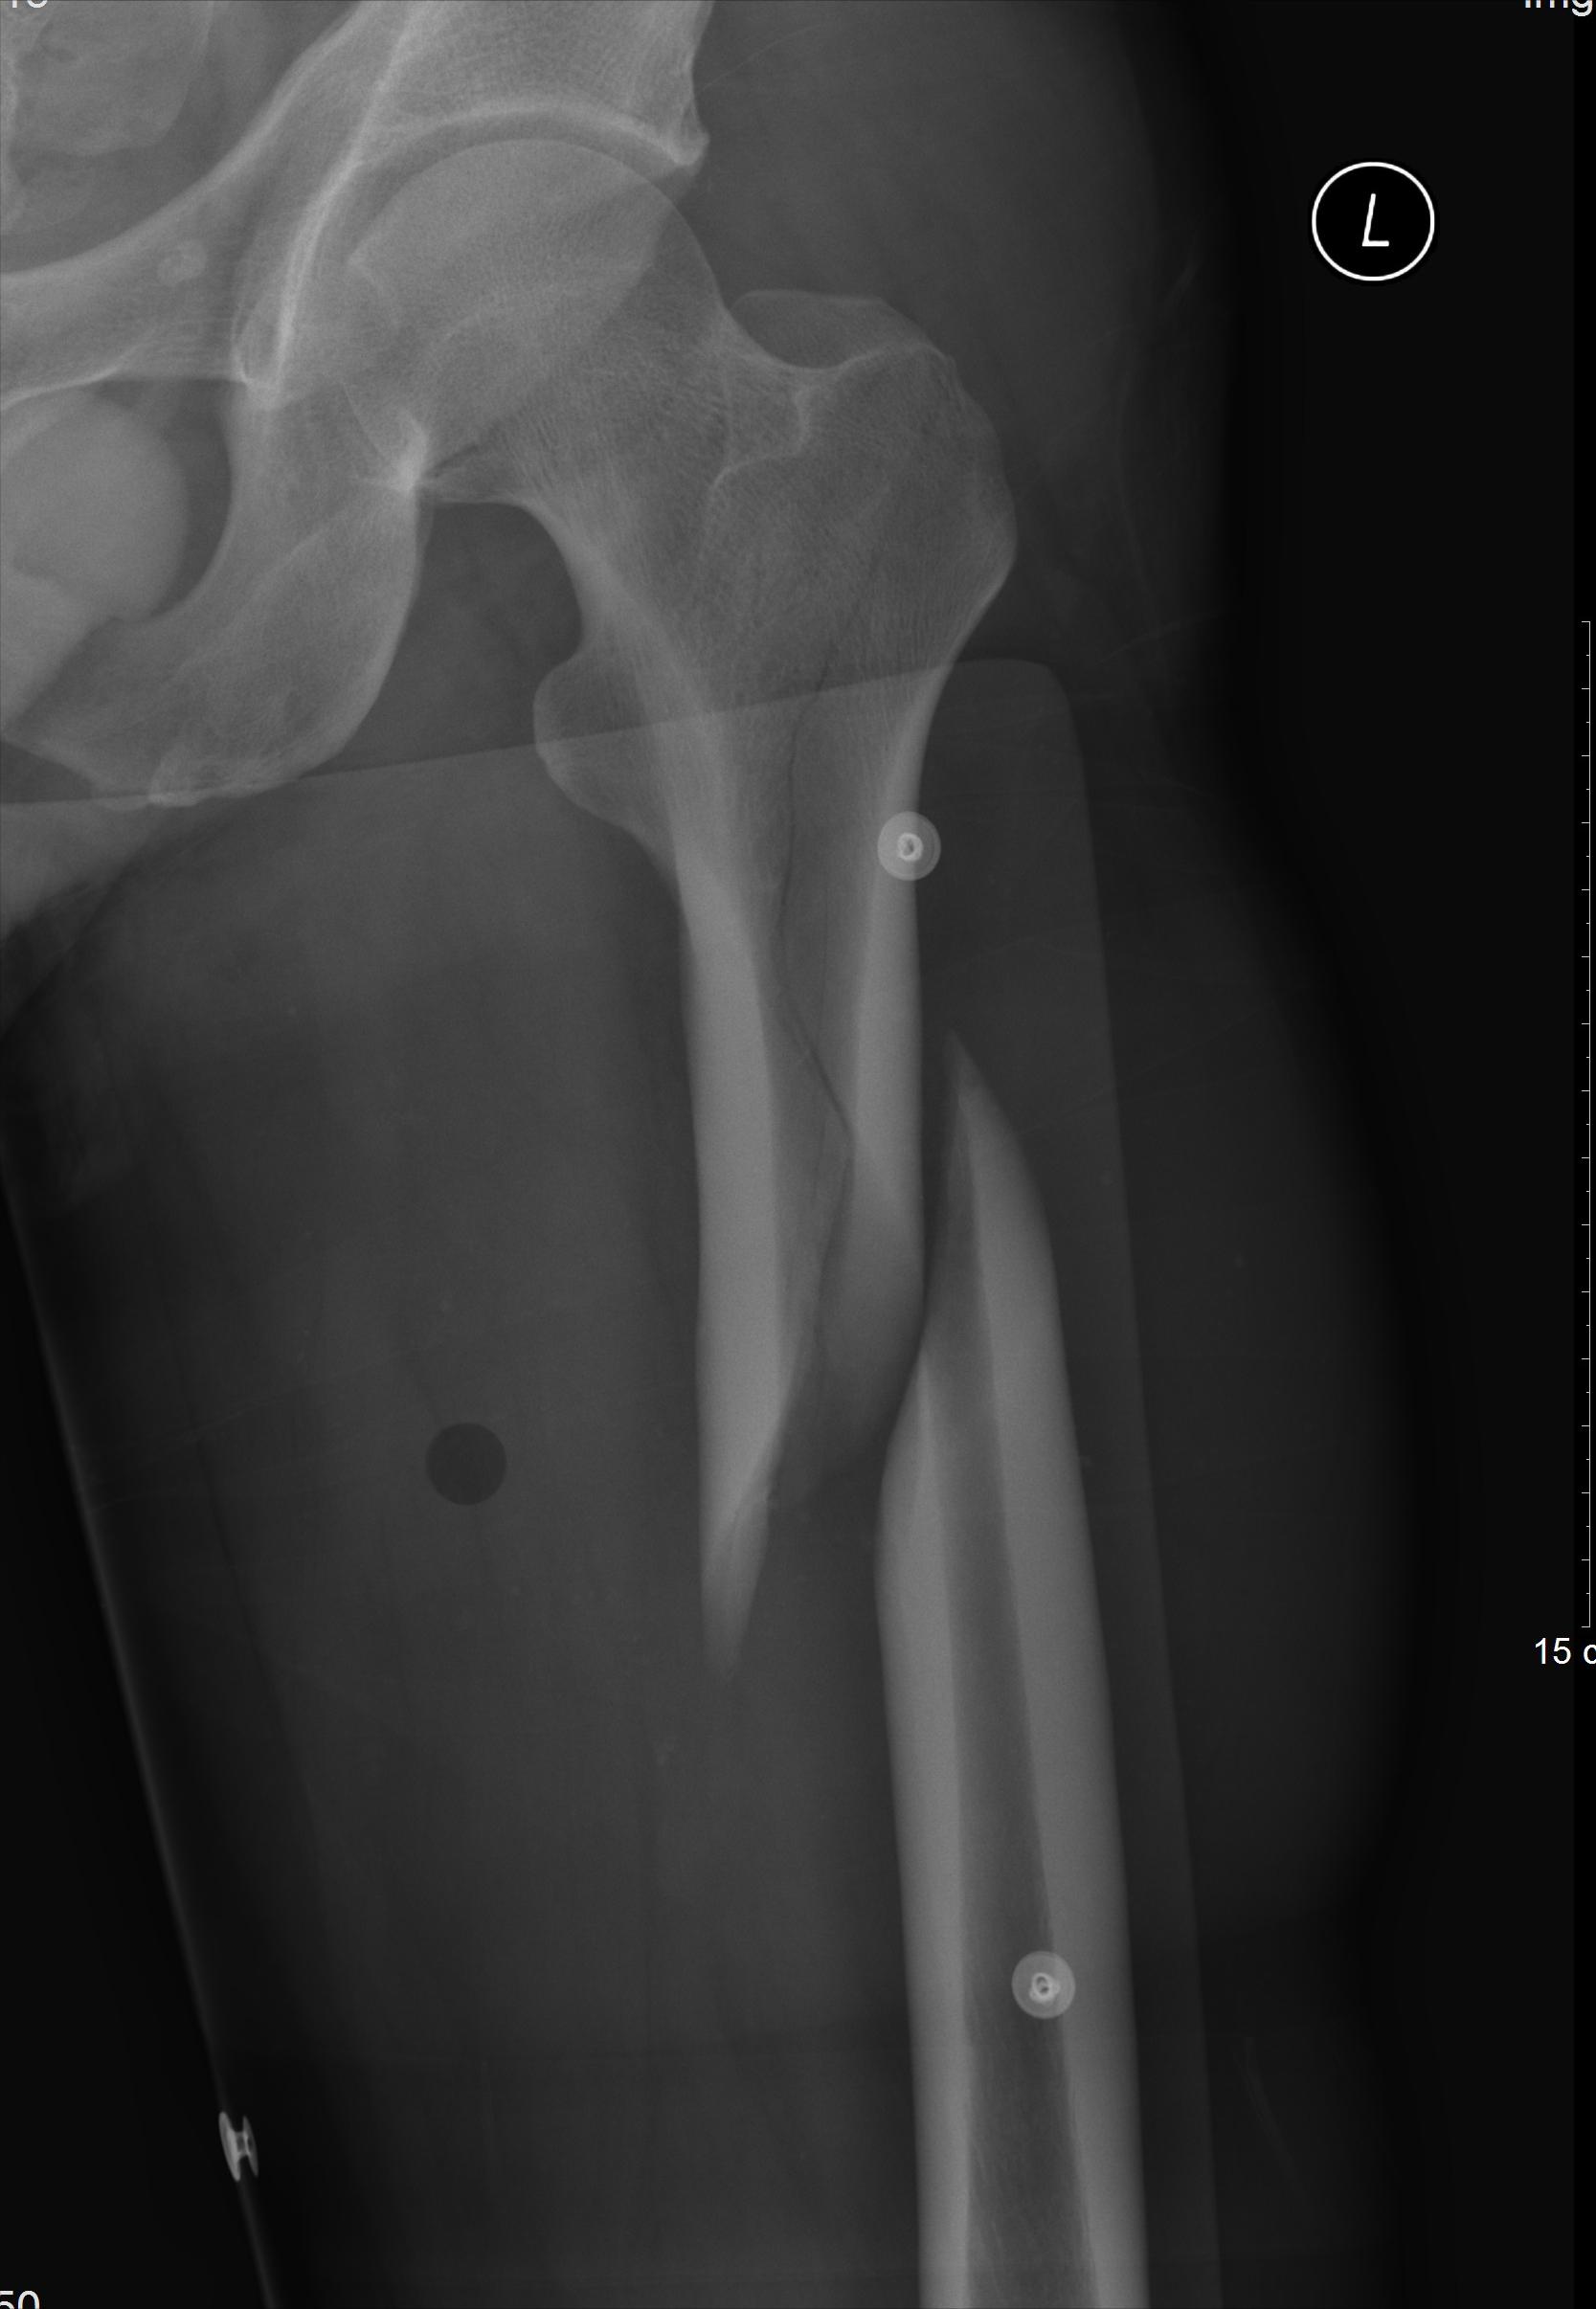

2、左股骨干骨折

左股骨中上段X片